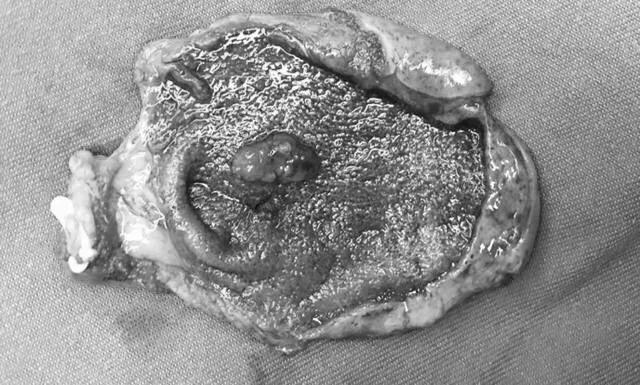

病理学分类:

胆固醇性息肉:胆固醇性息肉是最常见的胆囊息肉类型,占全部胆囊息肉样病变的85%左右。常表现为多发性,也可单发,息肉一般较小且增长缓慢。目前认为胆固醇性息肉不会癌变或癌变风险非常小。

胆固醇性息肉(多发息肉)